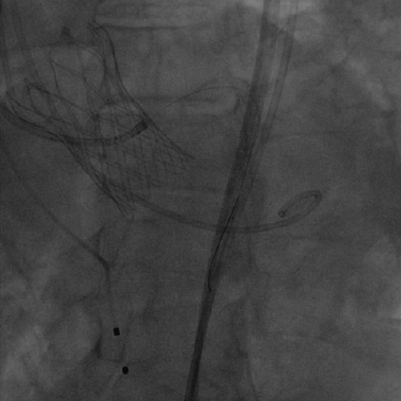

术中影像

主动脉根部造影和冠脉造影+PCI

瓣膜稳定释放和瓣膜释放后左冠显影正常